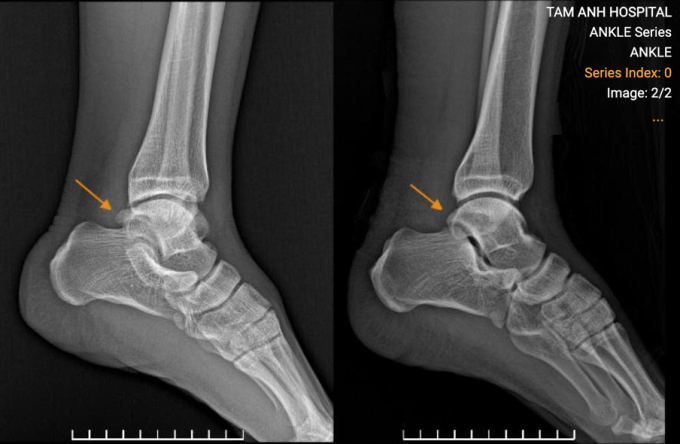

Xương thừa (chồi xương) ở gót chân anh Tuấn (bên trái) sau khi được nội soi cắt bỏ (bên phải). Ảnh: Bệnh viện Đa khoa Tâm Anh